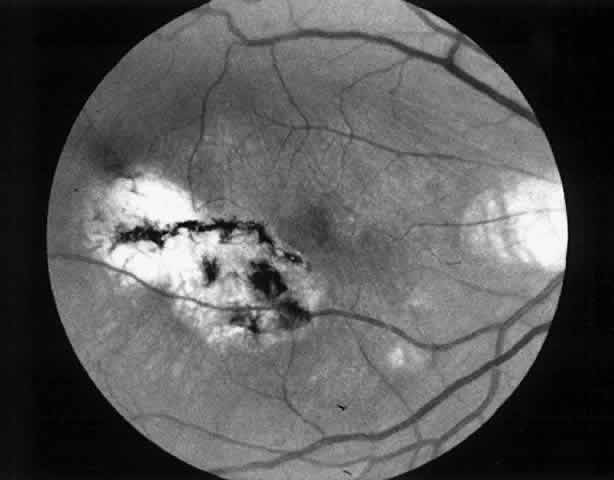

3. A 39-year-old patient with POHS developed a recurrent choroidal neovascular membrane involving the fovea with a decrease in vision to 20/100 (6/30) (Fig. 11). He underwent surgical excision but laser was not applied to the retinotomy site at the conclusion of the case. One month after surgery his vision improved to 20/30 (6/9) and the retinotomy was not noticeable (Fig. 12).

Fig. 11. Preoperative photograph of a 39-year-old patient with presumed ocular histoplasmosis syndrome (case 3). Visual acuity is 20/100 (6/30).

Fig. 12. Postoperative photograph (case 3). One month after surgery visual acuity is 20/30 (6/9). Retinotomy site is not noticeable.